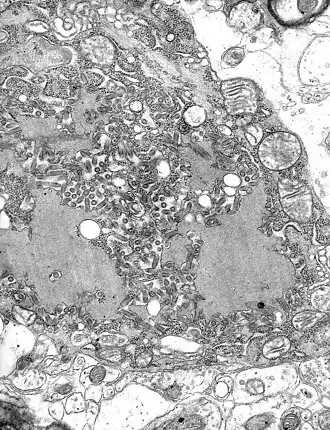

Micrografia com numerosos vírus da raiva (pequenas partículas em arredondadas em tom cinza escuro) e os corpúsculos de Negri, as maiores inclusões celulares patognomônicas na infecção da raiva.

Corpúsculos de Negri são eosinofílicas inclusões virais citoplasmáticas (espécie de "colonização" celular feita por vírus) localizadas nas células do cerebelo (células de Purkinje) do animal afetado pela raiva.

Apenas os vírus da raiva produzem uma inclusão exclusivamente no citoplasma.[1]